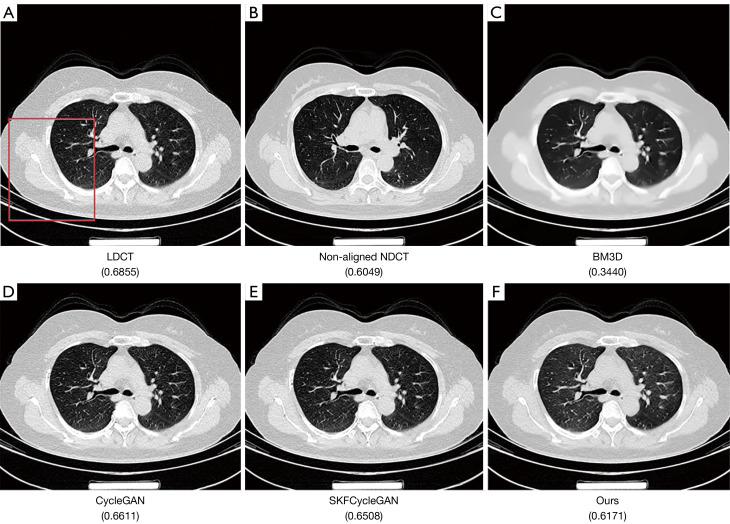

Within the domain of weakly supervised methods, our proposed model exhibited superior objective metrics on the simulated dataset when compared to CycleGAN and selective kernel-based cycle-consistent GAN (SKFCycleGAN): the peak signal-to-noise ratio (PSNR) was 43.9441, the structural similarity index measure (SSIM) was 0.9660, and the visual information fidelity (VIF) was 0.7707. In the clinical dataset, we conducted a visual effect analysis by observing various tissues through different observation windows. Our proposed method achieved a no-reference structural sharpness (NRSS) value of 0.6171, which was closest to that of the NDCT images (NRSS =0.6049), demonstrating its superiority over other denoising techniques in preserving details, maintaining structural integrity, and enhancing edge contrast.

结果

在弱监督方法领域,与CycleGAN和基于选择性内核的循环一致GAN(SKFCycleGAN)相比,我们提出的模型在模拟数据集上表现出更好的客观指标:峰值信噪比(PSNR)为43.9441,结构相似性指数测量(SSIM)为0.9660,视觉信息保真度(VIF)为0.7707。在临床数据集中,我们通过不同观察窗口观察各种组织进行了视觉效果分析。我们提出的方法实现了无参考结构清晰度(NRSS)值为0.6171,最接近NDCT图像的NRSS值(NRSS = 0.6049),表明其在保留细节、保持结构完整性和增强边缘对比度方面优于其他去噪技术。